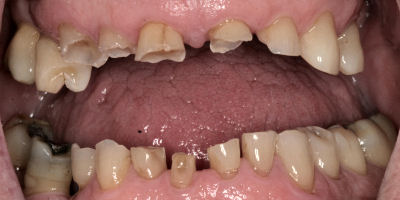

Opening Bite